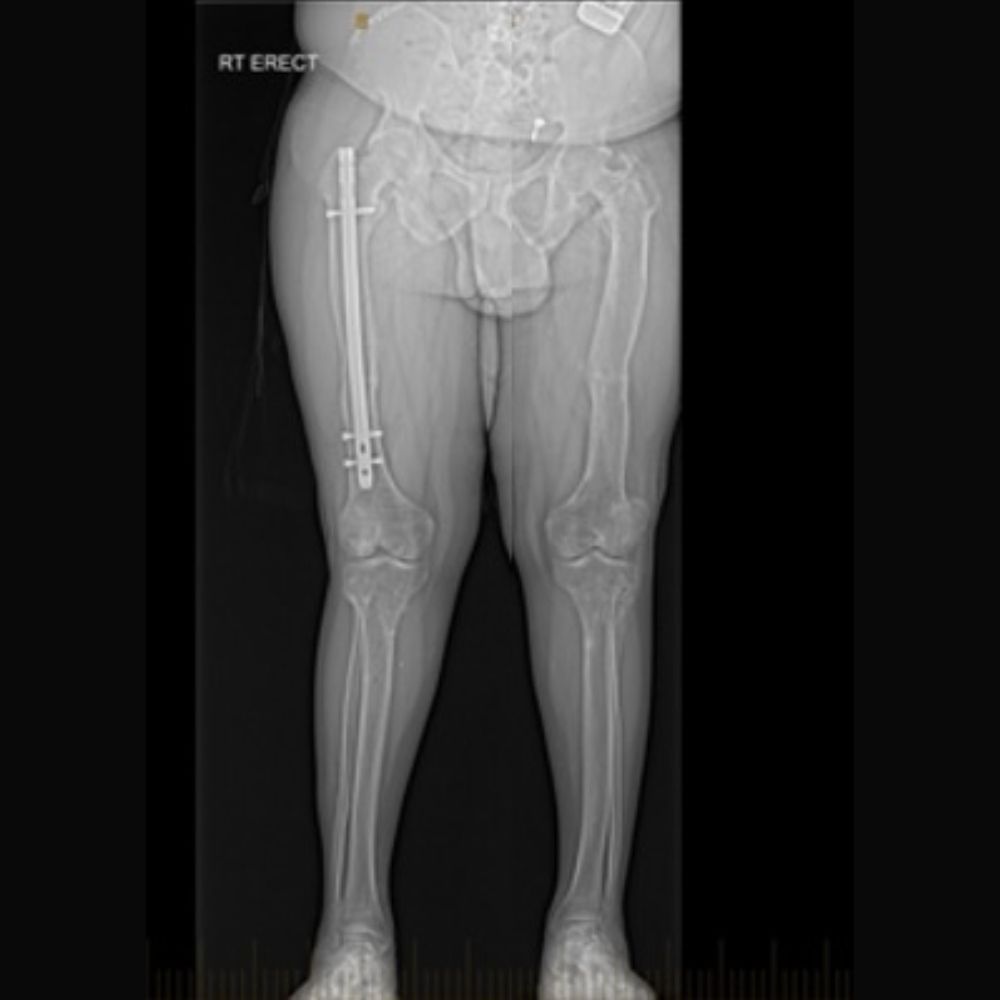

Asymmetric Knock Knee Due to Kidney Problems Through Childhood in 13 Year Old Girl

Adult with Correction of the Lower Limb Deformity due to Rickets